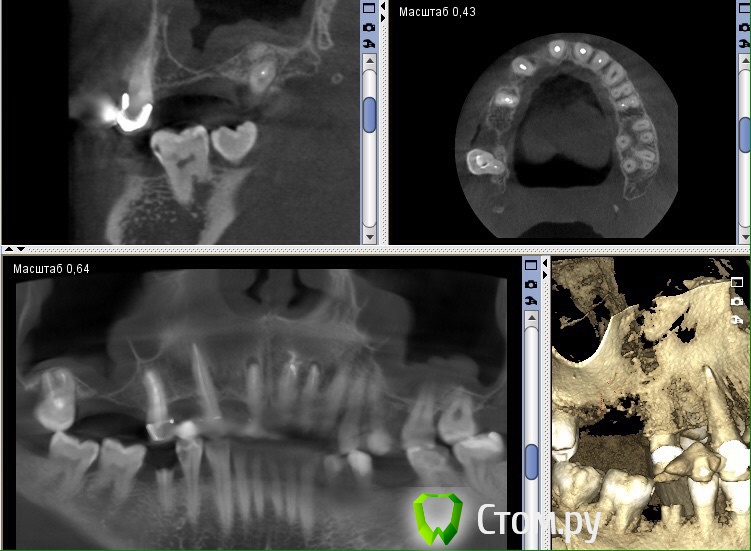

Фарид Расулыч Опубликовано 12 ноября, 2014 Поделиться Опубликовано 12 ноября, 2014 Есть пациент, человек, мужчина. Жалоб не предъявляет. Толщина в пазухе 5мм. Короткий вопрос: сначала лор потом синус? Ссылка на комментарий

Тимур86 Опубликовано 12 ноября, 2014 Поделиться Опубликовано 12 ноября, 2014 Кроме гипертрофии слизистой ничего не увидел...сразу синус имхо 2 Ссылка на комментарий

Фарид Расулыч Опубликовано 12 ноября, 2014 Автор Поделиться Опубликовано 12 ноября, 2014 В нагрузку Ссылка на комментарий

faity Опубликовано 12 ноября, 2014 Поделиться Опубликовано 12 ноября, 2014 если это не воспалительный процесс на данный момент, то работайте. до 10мм утолщение слизистой может быть, ничего страшного. Ссылка на комментарий

Bier Опубликовано 12 ноября, 2014 Поделиться Опубликовано 12 ноября, 2014 надо смотреть на соустье, если оно забито, то сначала к ЛОРу, а если свободно, то на синус ) 4 Ссылка на комментарий

Фарид Расулыч Опубликовано 12 ноября, 2014 Автор Поделиться Опубликовано 12 ноября, 2014 Так в том то и беда, что соустье не попадает в обзор... Ссылка на комментарий